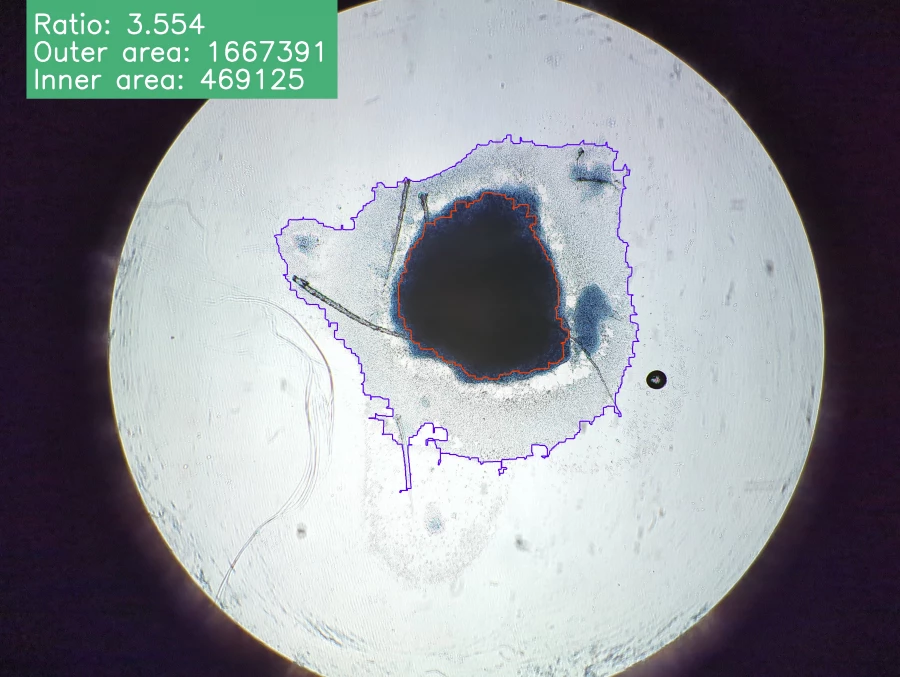

Наука. Снимки эксплантов

Когда эксплант растет в питательной среде, вокруг него формируется так называемая «зона роста» – тонкий, почти прозрачный слой делящихся клеток. Размер зоны – это ключевой показатель жизнеспособности клеток и показывает их реакцию на внешние воздействия, например, на новое лекарство.

Приложение для ученых

Сейчас ученые вынуждены вручную анализировать несколько планшетов с образцами под микроскопом: обводить зоны роста, подсчитывать их площадь. На одном планшете может находиться не менее 24 эксплантов. Это монотонная и трудоемкая работа, напоминает бумажную волокиту и отнимает у лаборантов несколько дней, которые они могли бы посвятить исследованиям.

«Мы создаем автоматизированную систему для анализа изображений эксплантов, – рассказывает Михаил Макеев. – Пользователь сможет загружать снимки на наш онлайн-сервис. Затем алгоритм на основе машинного обучения автоматически распознает и обводит эксплант и зону роста. После этого он проводит все необходимые расчеты и выдает готовый отчет. Это освободит время для более сложных научных задач».